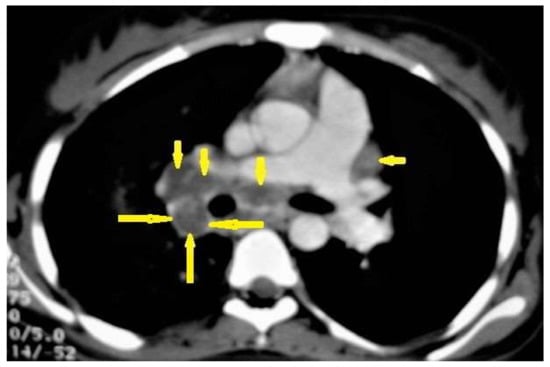

Figure 1. Primary TB in an 18-year-old man. Axial mediastinal-window CT image shows multiple enlarged mediastinal lymph nodes (short arrows), and right hilar lymph nodes are characterized by central low density and peripheral enhancement after contrast administration forming the rim sign (long arrows).

• Lymphadenopathy (Figure 1) is the most common radiological manifestation of primary TB. It is characterized by right paratracheal, hilar, or subcarinal enlarged LNs with or without parenchymal abnormalities. Lymphadenopathy is more likely to occur in children than in adults and may cause pulmonary atelectasis.

A CT is more effective than a chest X-ray (CXR) for the detection of LNs, which are characterized by a low density center and peripheral enhancement after contrast administration, which form the “rim sign” [1,13]. Bilateral hilar lymphadenopathy is an important differential diagnosis of many benign and malignant diseases, such as sarcoidosis and lymphoma [13].